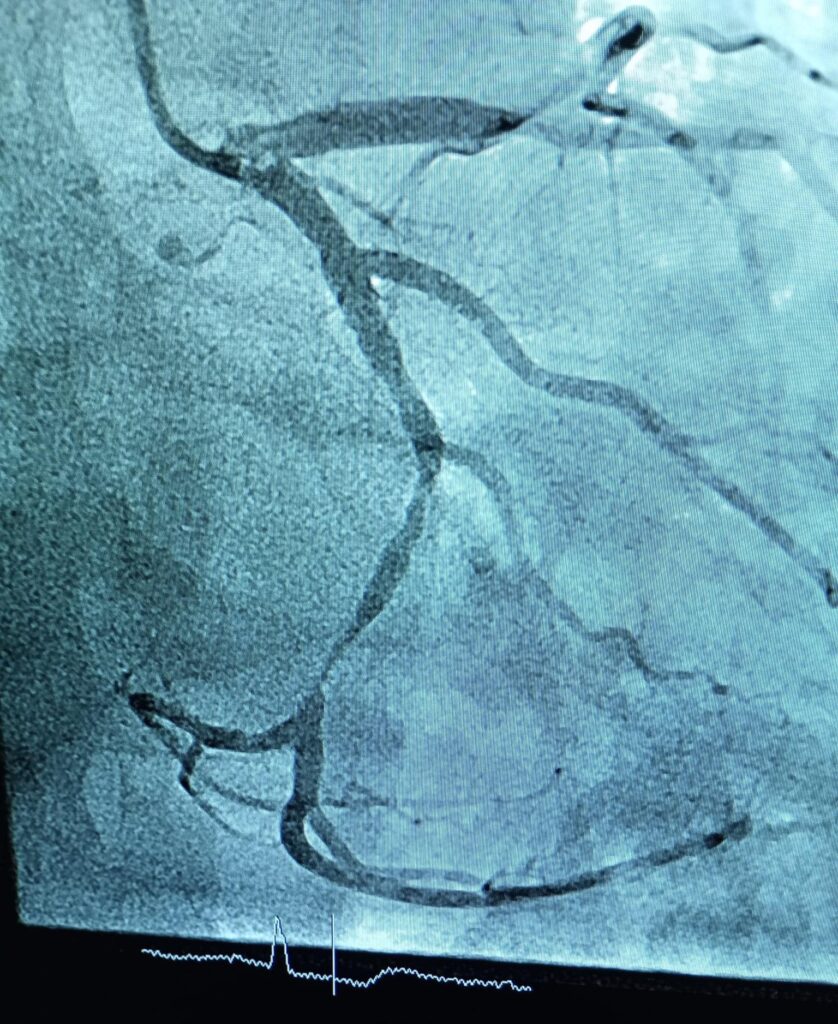

Spitalul Județean de Urgență Zalău marchează o nouă etapă importantă în dezvoltarea serviciilor medicale, odată cu realizarea primelor angiografii coronariene cu intervenții PCI și montare de stent, proceduri efectuate în premieră atât la nivelul unității medicale, cât și al județului Sălaj.

Procedurile au un rol atât diagnostic, cât și terapeutic, oferind pacienților cu afecțiuni vasculare coronariene posibilitatea de a fi investigați și tratați local, fără a mai fi nevoiți să se deplaseze în alte centre medicale din țară. Pentru bolnavii cardiaci, acest lucru înseamnă acces mai rapid la tratamente salvatoare și șanse mai mari de recuperare.

Primele cinci intervenții de acest tip au fost realizate cu succes de echipa Compartimentului de Cardiologie Intervențională, în colaborare cu specialiștii Secției de Anestezie și Terapie Intensivă, sub coordonarea medicului Horațiu Comșa. Reprezentanții spitalului au transmis mulțumiri și felicitări echipelor medicale implicate, pentru profesionalismul și rigoarea de care au dat dovadă.

După debutul programului de implantare a stimulatoarelor cardiace în cadrul Compartimentului de Cardiologie Intervențională, astăzi marcăm o nouă premieră pentru spital și pentru județul Sălaj: realizarea primelor angiografii coronariene cu intervenții PCI și montare de stent.

Aceste proceduri au rol diagnostic și terapeutic și reprezintă, pentru prima dată, posibilitatea ca pacienții cu afecțiuni vasculare coronariene să fie investigați și tratați local, în cadrul SJUZ, fără a mai fi nevoiți să se deplaseze în alte centre.